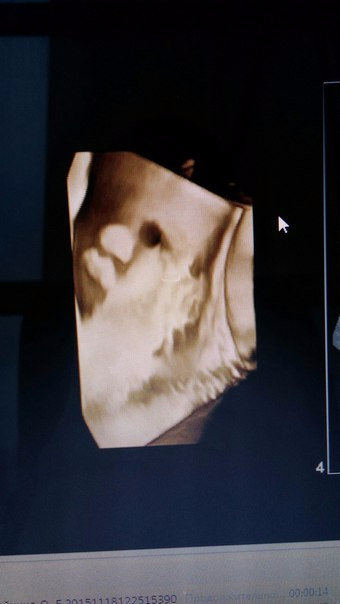

Наши 37 недель.

32 недели... Узи в 30 недль было абсолютно для нас не интересным, пошли вместе с Глебом, чтобы он на братика посмотрел, а у нас он лег поперек и ничего не видно было.

36 недель... Сходили на узи еще раз, Глеб посмотрел, все довольны!